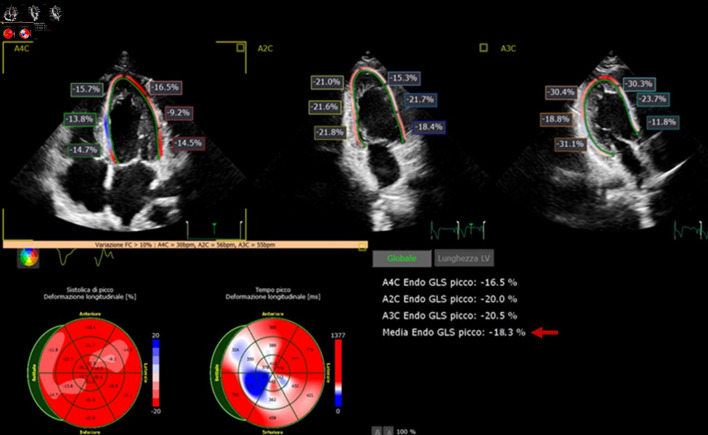

Left ventricular non-compaction (LVNC) is a rare primary cardiomyopathy with genetic etiology, resulting from an abnormality of myocardial development during embryogenesis. It carries an elevated risk of left ventricular dysfunction, thromboembolic events and malignant arrhythmias. We report the case of LVNC associated with paroxysmal atrial fibrillation and ankyrin 2 (ANK2) mutation at the genetic test. An 18-year-old competitive athlete visited our medical center to undergo the diagnostic investigations protocol preparatory to the release of the suitability for competitive practice. The echocardiographic examination shows LVNC without ventricular remodeling (left ventricular ejection fraction (LVEF) 53%, global longitudinal strain (GLS) -18.3%). The echocardiographic diagnosis was confirmed by cardiac magnetic resonance imaging (cMRI), which revealed dense hypertrabeculation in the left ventricular apex and lateral wall. The cardiogenetic investigation showed a c.9145C>T variant (p.Arg3049Trp) identified in the ANK2 gene. This mutation is associated in the literature with rare cases of LVNC. The patient underwent an extended Holter monitoring which excluded ventricular arrhythmic events but showed two brief episodes of paroxysmal atrial fibrillation. Despite the absence of significant ventricular remodeling, considering the presence of paroxysmal atrial fibrillation and the presence of a mutation in the ANK2 gene, which has several variants related to high-risk phenotypes, it has been decided to suspend the competitive practice, and is defined an adequate clinical-diagnostic follow-up.